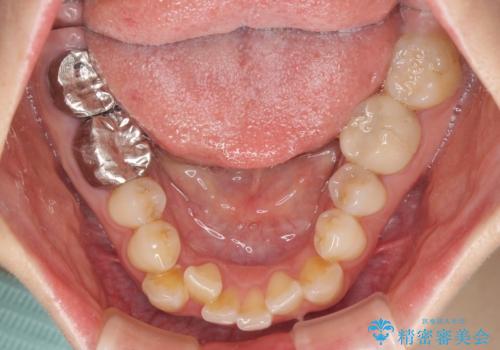

【モニター】前歯のデコボコと奥歯の虫歯 インビザライン治療と奥歯のセラミック治療

- 前歯のデコボコと奥歯の虫歯を気にして来院された患者様です。

主に下顎歯列全体の後方移動とIPR(歯と歯の間を削る)によってデコボコが解消するように設計し、インビザラインにより治療を行うこととしました。

矯正治療後半に下顎左右奥歯をセラミッククラウンにて補綴し、その後インビザラインによる歯列の仕上げを行うこととしました。

下顎前歯の叢生が速やかに改善されたため、1年3か月で治療を終えることができました。

下顎前歯は後戻りを起こしやすいため、舌側を細いワイヤーで固定することで後戻り対策を行っています。